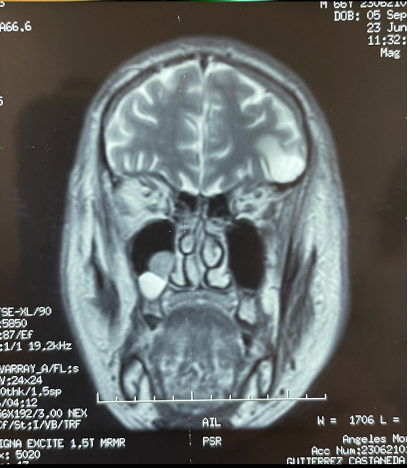

RMN: T2: MUCOCELE ES LA BOLITA DE ABAJO PORQUE TODO LO LIQ SE VE HIPERINTENSO. LA OTRA SEGURO SEA UN PÓPILO O UN TUMORCITO.